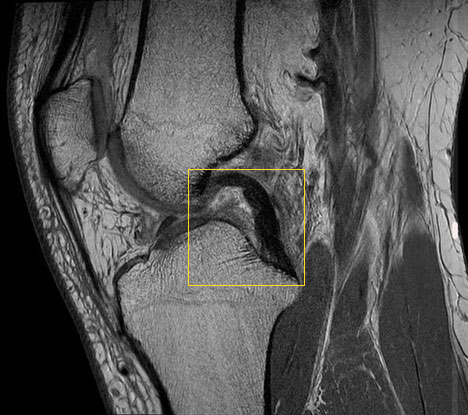

Untersuchung des Kreuzbandrisses mit Kernspintomografie (MRT)

Die im Röntgen oder durch klinische Untersuchungen nicht eindeutig feststellbaren Kreuzbandrisse kann eine MRT (Magnetresonanztomografie) viel besser darstellen.

Schwierig wird die Diagnose mittels MRT erst, wenn das Kreuzband nicht ganz gerissen ist, sondern nur gedehnt ist bzw. eine Teilruptur erlitten hat.

Teilrupturen des Kreuzbandes kann die Bildgebung nicht sicher darstellen. Man erkennt nur schwer, in welchen Anteilen das Kreuzband noch intakt ist. In diesen Fällen muss der Kniespezialist mit viel Erfahrung die Überbeweglichkeit des Kniegelenks im Vergleich zum anderen Knie überprüfen (Schubladentest).

Diagnose von Knochenödemen nach Kreuzbandriss

Häufig resultieren aus Distorsionsverletzungen, die zum Kreuzbandriss führen, auch Begleitverletzungen und Knochen-Knorpelschäden. Die Kernspintomografie kann diese sogenannten Bone Bruises anhand der Flüssigkeitseinlagerung im Knochen nachweisen.

So haben in der MRT über 80 % aller Patienten mit Kreuzbandriss ein sogenanntes Bone Bruise: Das ist ein mechanisches Trauma des Knochens, das zu sichtbaren Ödemen (Flüssigkeit im Knochen) führt. Nach Abheilen des Ödems ist es nicht mehr unmittelbar schmerzhaft. In vielen Fällen wird der Knorpel an diesen Stellen aber weich und ist weniger leistungsfähig. Bei Nachuntersuchungen zeigen sich an 50 % der Stellen mit Bone Bruise auch Knorpelerweichungen und Knorpelschäden.

Meniskus-MRT nach Kreuzbandriss

Die Magnetresonanztomografie (MRT) kann auch einen eventuellen Meniskusriss als Begleitverletzung des Kreuzbandrisses nachweisen. Diese Information ist wichtig für die Planung der Therapie. Manche Meniskusläsionen erfordern eine operative Meniskusnaht. Kleine Längsrisse in der Peripherie des Meniskus können auch konservativ behandelt werden.

Welche Schwierigkeiten bereitet die Diagnosestellung?

Ein kompletter Bandabriss verläuft häufig symptomarm. Teilrupturen sind von kompletten Abrissen in der klinischen Untersuchung schwer zu unterscheiden. Ergebnisse von Röntgen- sowie Kernspinuntersuchungen ergeben nicht selten fälschlicherweise negative Befunde. Man sieht also im Bild ein scheinbar intaktes Kreuzband, dessen innere Struktur – und damit auch seine Funktion – deutlich zerstört ist. Bei diesen falsch-negativen Befunden scheint das Kreuzband anatomisch intakt, obwohl es in Wirklichkeit keine Funktion mehr ausübt.

Das Kreuzband besteht aus vielen Einzelfasern, die mit einer Hüllstruktur umgeben sind – ähnlich wie bei einem ummantelten Telefonkabel. Die Fasern reißen häufig im Inneren, während die Hülle noch intakt ist. Bleibt die Umhüllung unversehrt, misslingt der Nachweis des Kreuzbandrisses im Kernspin, weil die Struktur äußerlich intakt zu sein scheint.